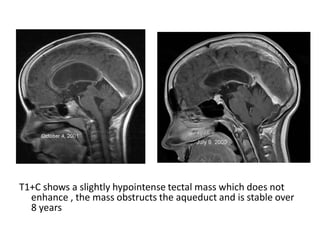

T1+C shows a slightly hypointense tectal mass which does not

enhance , the mass obstructs the aqueduct and is stable over

8 years

T1+C shows aslightly hypointense tectal mass which does not enhance , the mass obstructs the aqueduct and is stable over 8 years